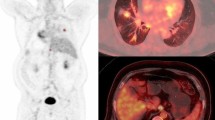

PET/CT images in a 53-year-old woman with adenocarcinoma stage IIIA (T3N1, primary tumour TV in red) illustrating a mismatch between a high decrease in TV and TLG and increasing SUVmax ratios. The baseline (a: coronal view, b: 3D view) and follow-up (c: coronal view, d: 3D view) scans were performed before and after three cycles of induction chemotherapy. SUVmax, TVF and TLGF ratios were respectively 1.25, 0.2 and 0.2. Right upper lobectomy with mediastinal LN dissection was performed. At the most recent follow-up (24 months), the patient was still alive with no evidence of recurrence